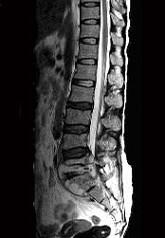

问题 男,35岁,曾有结核病史,现有午后发热,夜间盗汗等,腰部疼痛,活动时加重,休息后减轻,请结合所提供图像,选择最佳答案 ( )

选项 A、腰椎结核 B、多发性骨髓瘤 C、腰椎骨转移 D、腰椎退行性变 E、骨巨细胞瘤

答案 A